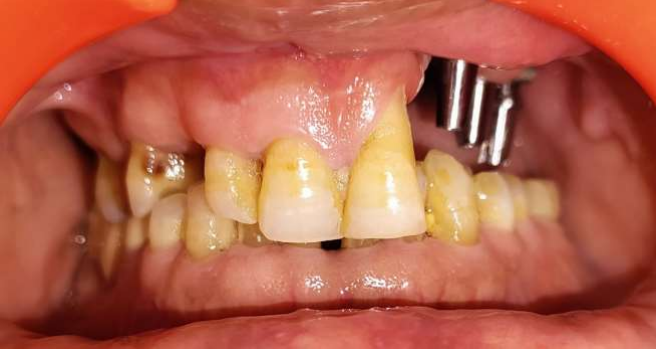

A 55-year-old man was referred to the Department of Prosthodontics with complaints of hypernasal speech, nasal regurgitation, and oroantral communication. He had undergone post Mucormycosis partial maxillectomy (Left Maxilla) and had not received any prosthetic rehabilitation (Figure 1). The patient presented with oroantral communication and difficulty in speech and mastication.

The extraoral and intraoral examination revealed the absence of the maxilla, hard palate, and nasal floor of the left side. The nasolabial fold was obliterated, with drooping of the corners of his mouth, and insufficient upper lip support. The patient was classified as having Brown II maxillectomy defect with the aim of the reconstruction being to obturate the defect and restore the facial profile and function. The main goal was to deliver a patient specific implant supported prosthesis in which the intaglio surface of the prosthesis would share the support and stabilization functions and the retention would be dependent on the implants.

Figure 1: Maxillary defect post Mucormycosis

Figure 1